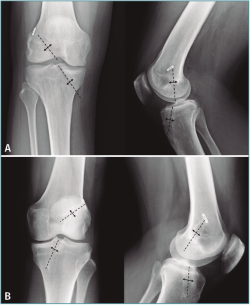

Evaluación del ensanchamiento de los túneles

El ensanchamiento óseo de los túneles se calculó comparando la medición del diámetro comprendida entre los márgenes óseos del túnel tanto femoral como tibial en las radiografías AP y lateral del postoperatorio inmediato y tras un mínimo de 6 meses de seguimiento. Esta medición se calculó midiendo la distancia comprendida entre los márgenes escleróticos del túnel formando una línea perpendicular al eje del túnel femoral y tibial, expresada en milímetros. Si el diámetro del control radiográfico del postoperatorio inmediato no fue posible por la escasa visualización de los márgenes, se utilizó el diámetro intraoperatorio del túnel (Figura 2).

Figura 2. Ensanchamiento de túnel femoral y tibial en radiografías anteroposterior y lateral midiendo la distancia comprendida entre los márgenes escleróticos del túnel formando una línea perpendicular al eje del túnel femoral y tibial, expresada en milímetros. A: grupo A (anterógrado); B: grupo R (retrógrado).